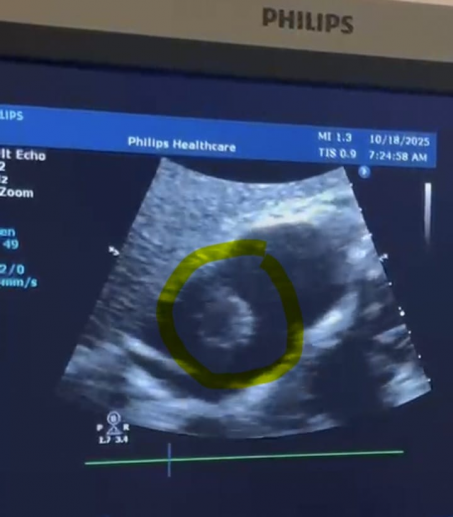

وذكر اعلام  صحة النجف :"  ان فحص الإيكو القلبي  اظهر وجود كتلة غير طبيعية داخل القلب مصحوبة بانصباب تأموري متوسط. وعلى ضوء ذلك، تم نقل المريضة على وجه السرعة إلى وحدة الإنعاش لمتابعة حالتها عن كثب على مدى عدة أيام. مبينا " وبعد تأكيد استقرار الحالة، تم التنسيق مع مركز القلب المفتوح لإجراء فحص الرنين المغناطيسي القلبي (MRI)، الذي كشف عن وجود ورم في الأذين الأيمن للقلب من نوع أنجيوساركوما (Cardiac Angiosarcoma)، وهو أحد أندر الأورام القلبية على المستوى العالمي، إذ لا تتجاوز نسبة الإصابة به 0.056% من مجموع الأورام السرطانية.